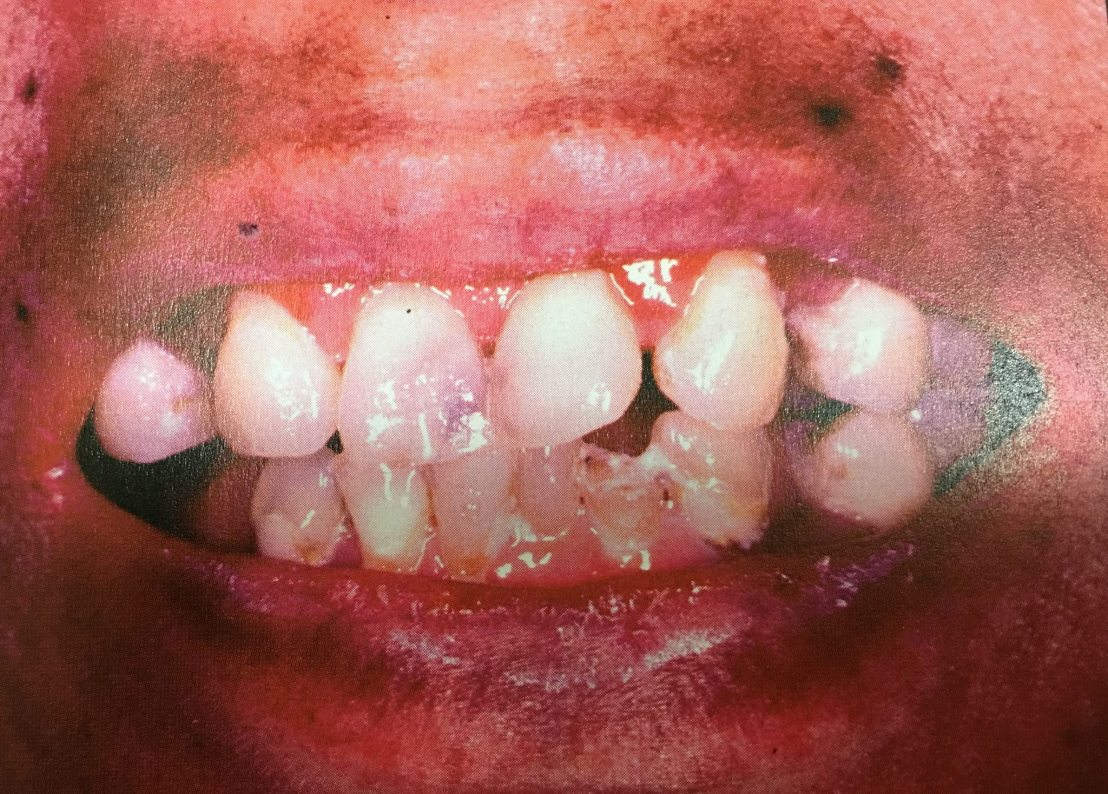

ในบรรดาโรคทั้งหมดที่มีในเล่มนี้ บทที่ 10 คือ โรคที่โหดสุด ความรุนแรงสูงสุดครับ

เรียกอีกชื่อว่า Epiloia = Epi=Epilepsy+loi=low I.Q.+a=Adenoma sebaceum=รอยโรคที่ใบหน้า

ความผิดปกติที่ฟัน ก็ดูยากมาก เพราะเหมือน TSL (Tissue surface loss) ทั่วไป

ดูที่ฟันอย่างเดียว หมดสิทธิ์ ไม่มีทางเลย

Gingival fibroma ที่เหงือกก็ดูยาก เพราะถูกบดบังจากผลของยากันชัก แต่จากการซักประวัติและรอยโรคที่ใบหน้าจะทำให้ Dx โรคนี้ได้ทันทีครับ (ถ้าใครอยากรู้ลองกดดู ที่นี่ ครับ)